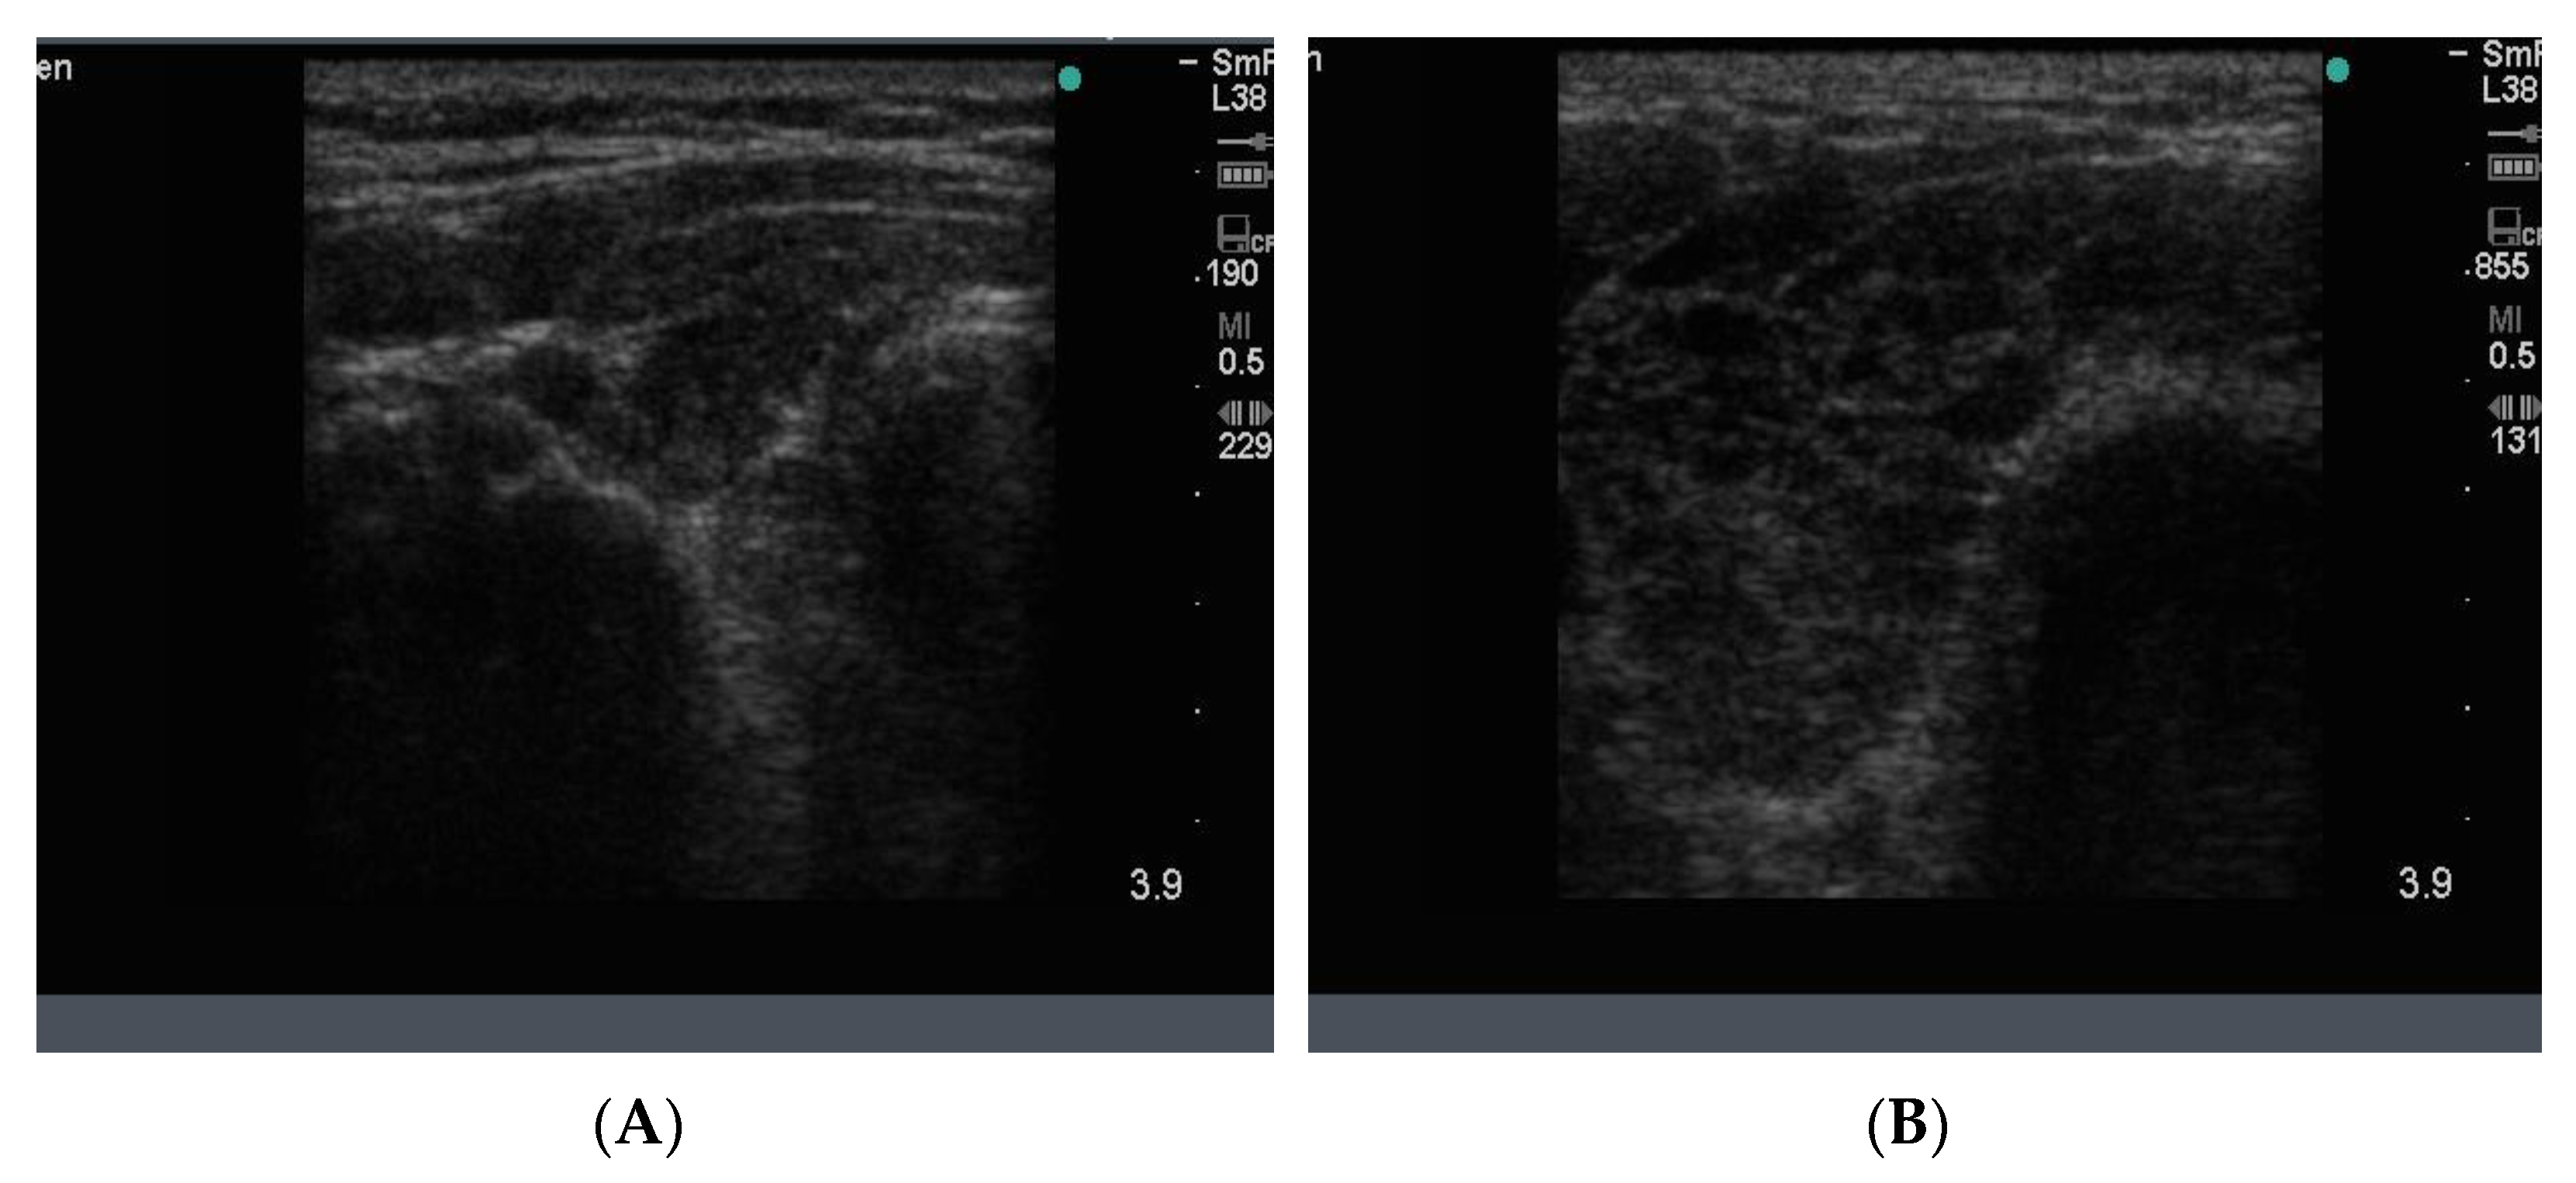

In Hashimoto thyroiditis the blood supply to the gland increases during the early inflammatory stages, but later, when the inflammation has burnt out and the gland is scarred and empty, the overall blood supply is markedly reduced. Examples of the two types of end stage disease are seen in Figure 16.

Figure 16.

Thyroid ultrasound findings in 2 patients with different features of late-stage Hashimoto thyroiditis. In (A) the dominant feature is diffuse hypo echoicity, seen as black “holes” indicating the absence of thyroid tissue, some scarring, decreased vascularity and architectural damage in an overall enlarged gland. In (B), the thyroid gland is now shrunken, scarred and shrivelled with pseudo nodules and scattered fibrous bands in a small gland; this is the final stage and the patient has no thyroid function.